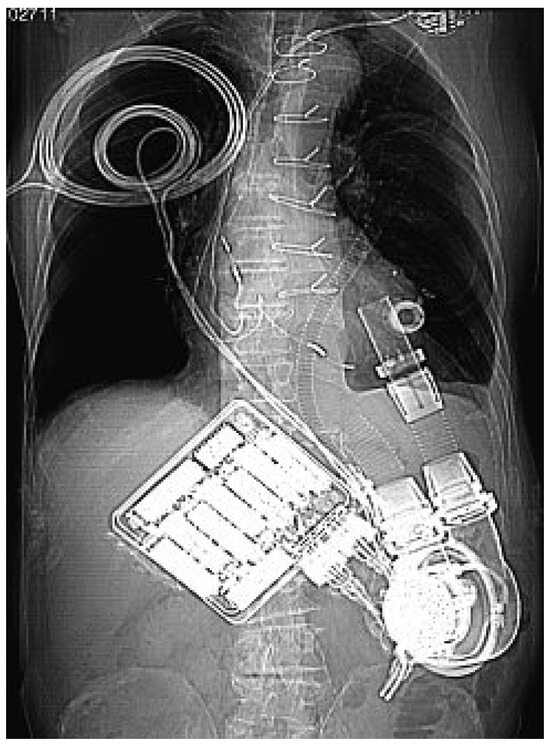

Links-Ventrikuläre Assist Devices—Indikationen und Möglichkeiten

by Ludwig K. von Segesser, Piergiorgio Tozzi, Enrico Ferrai, Sandra Bommeli, Lars Niclauss, Dominique Delay, Philippe Gersbach, Michel Hurni, Bettina Marty, Patrick Ruchat and Frank Stumpe

Heart failure not responding to medical therapy is either due to left ventricular failure, right ventricular failure or bi-ventricular failure. Left ventricular assist devices are designed for left ventricular mechanical circulatory support and not suitable for treatment of advanced global cardiac failure which [...] Read more.

Heart failure not responding to medical therapy is either due to left ventricular failure, right ventricular failure or bi-ventricular failure. Left ventricular assist devices are designed for left ventricular mechanical circulatory support and not suitable for treatment of advanced global cardiac failure which deteriorates rapidly towards irreversible multi organ failure. Although temporary right ventricular support may be necessary during left mechanical circulatory support, it should be the goal that this is the exception and not the rule. This statement is based on the experience, that predominantly left ventricular failure can be handled well with the timely application of modern implantable left ventricular assist devices which allow usually for relative rapid recovery towards a quite normal life.

We mean here not only weaning from the ventilator, extubation, mobilisation, and the transfer from the intensive care unit to the general hospital ward, but rather the discharge home with a quite good quality of life over a longer time frame despite the machine dependence which requires in our program a weekly outpatient check of the patient with his hard and software. Full article

Figure 1